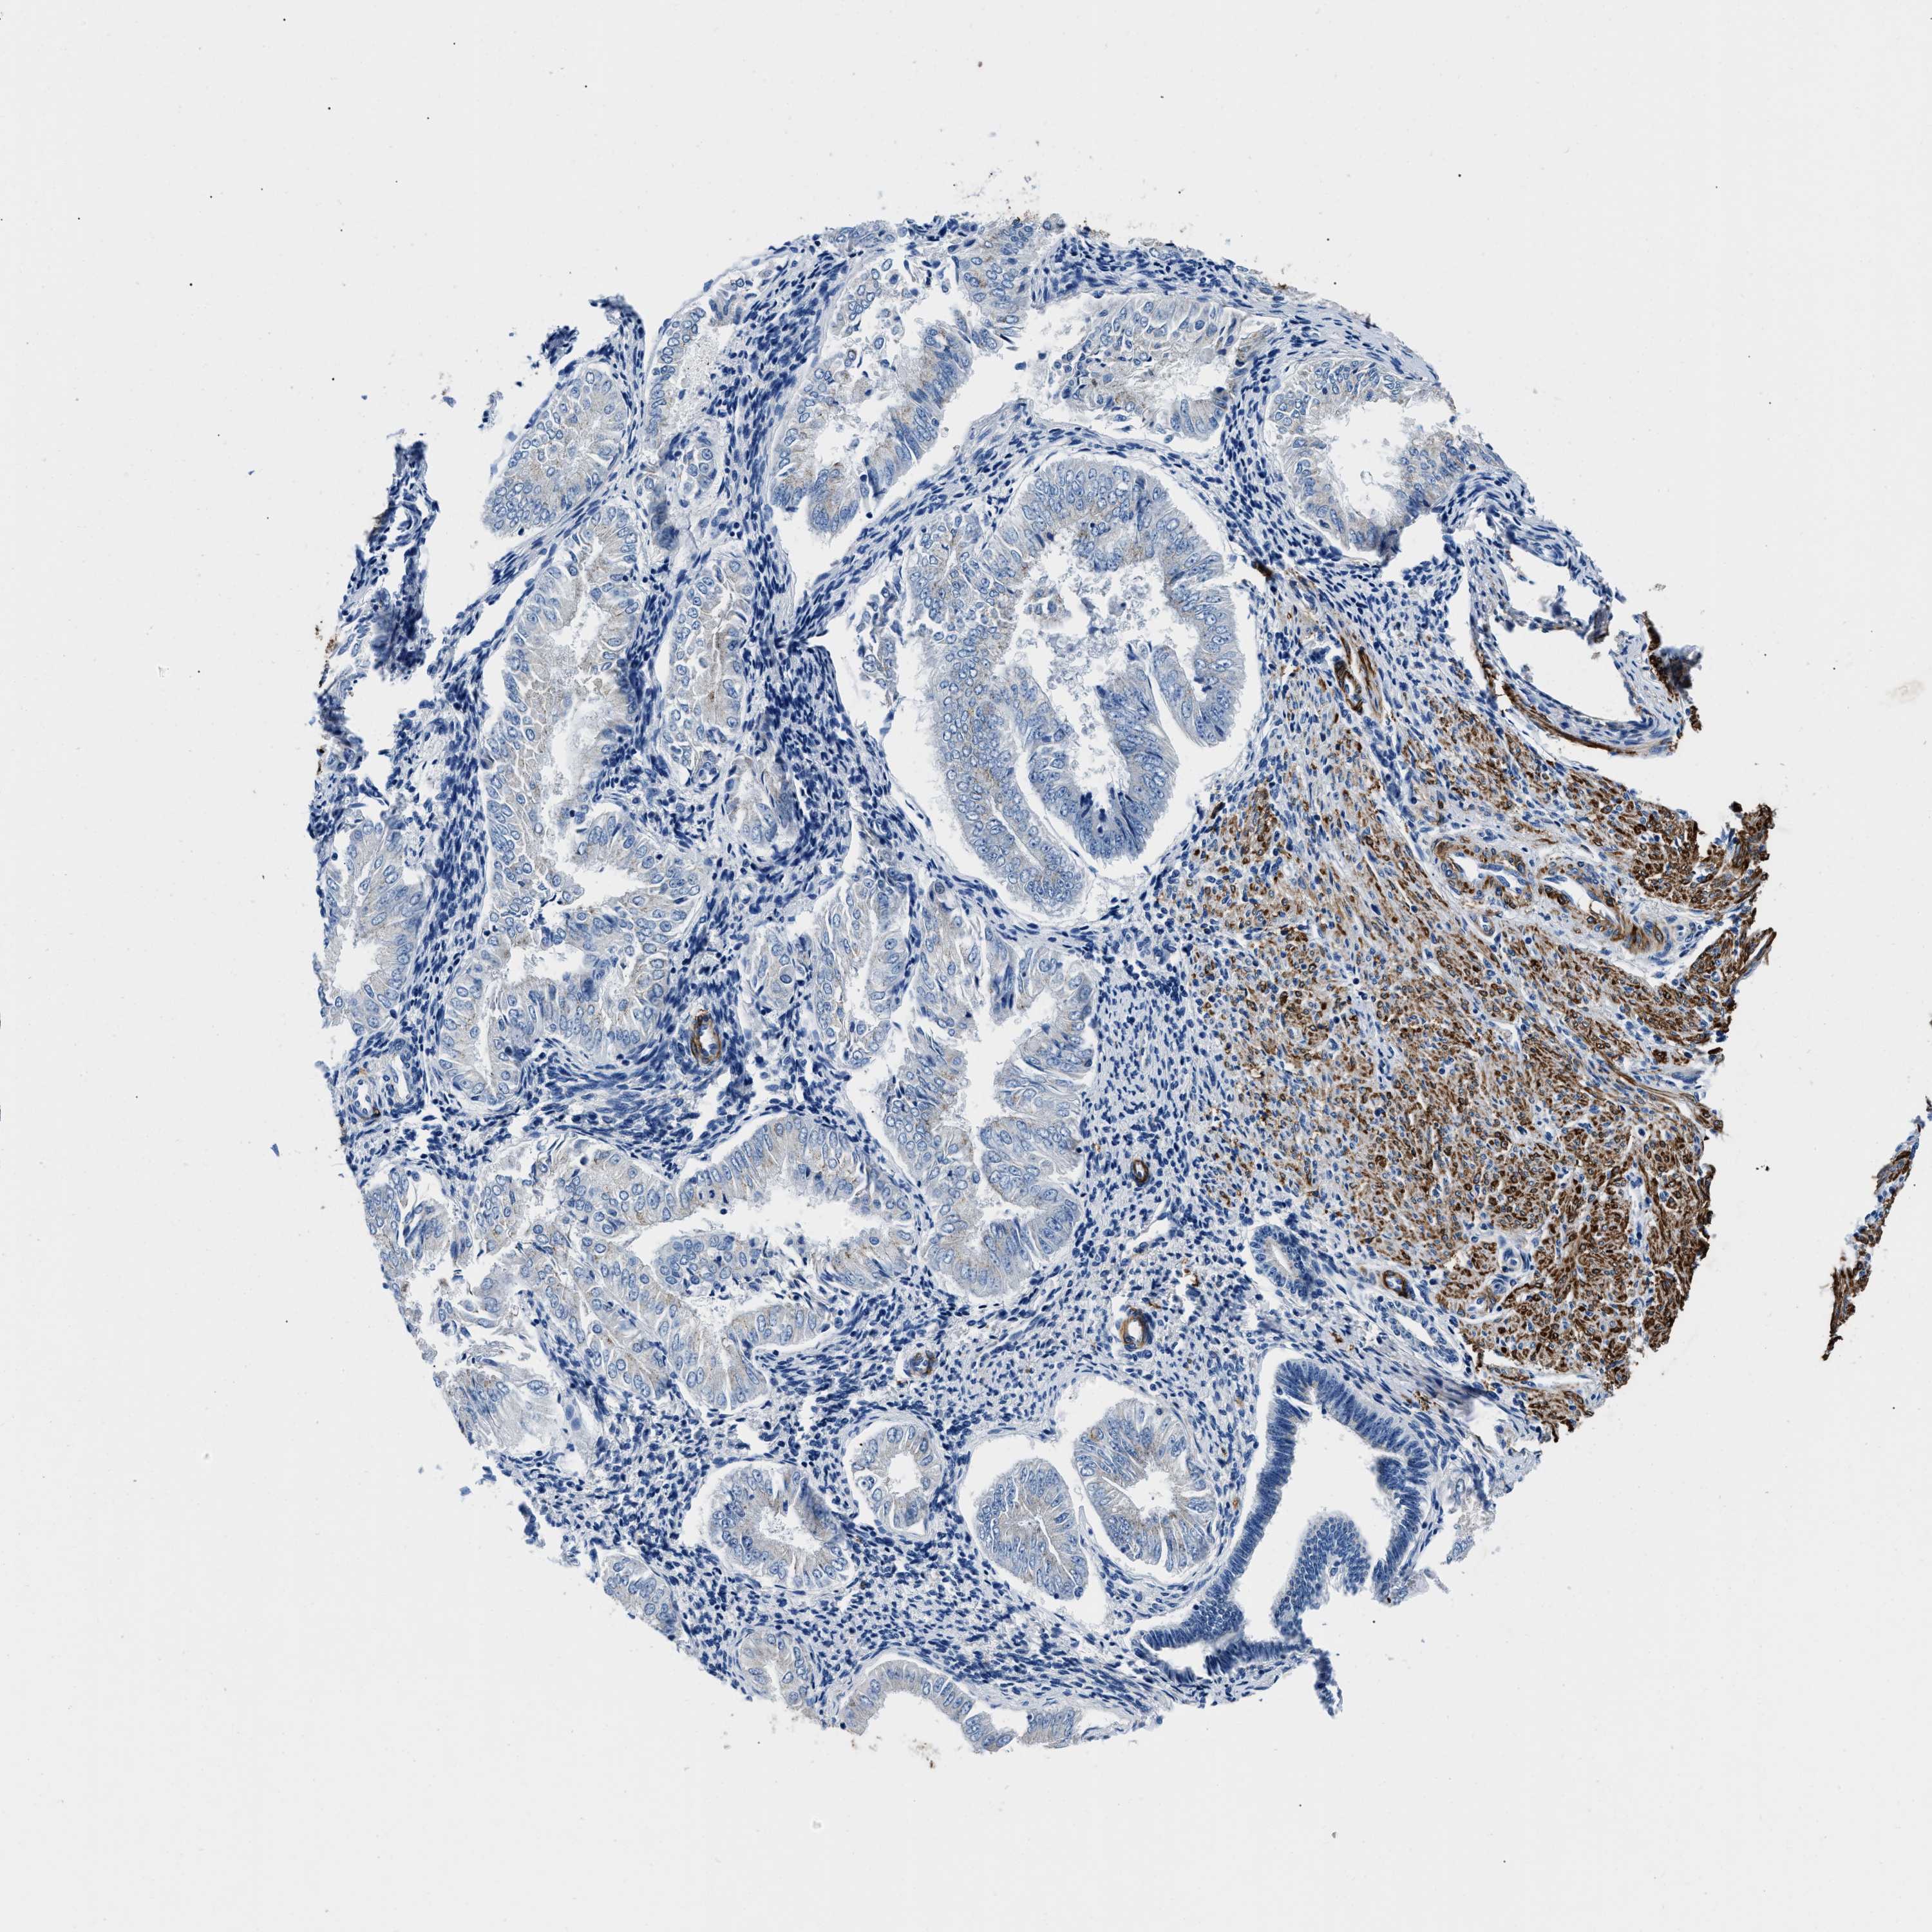

ENDOMETRIAL CANCER - Protein expressioni

A mouse-over function shows sample information and annotation data. Click on an image to view it in a full screen mode. Samples can be filtered based on level of antibody staining by selecting one or several of the following categories: high, medium, low and not detected. The assay and annotation is described here.

Note that samples used for immunohistochemistry by the Human Protein Atlas do not correspond to samples in the TCGA dataset.

Antibody stainingi

Antibody staining in the annotated cell types in the current human tissue is reported as not detected, low, medium, or high, based on conventional immunohistochemistry profiling in selected tissues. This score is based on the combination of the staining intensity and fraction of stained cells.

Each image is clickable and will lead to virtual microscopy that enables deeper exploration of all samples and also displays staining intensity scores, fraction scores and subcellular localization as well as patient and tissue information for each sample.

Antibody HPA016631

Staining

High

Medium

Low

Not detected

Intensity

Strong

Moderate

Weak

Negative

Quantity

>75%

75%-25%

<25%

None

Location

Nuclear

Cytoplasmic/membranous

Cytoplasmic/membranous,nuclear

Adenocarcinoma, NOS